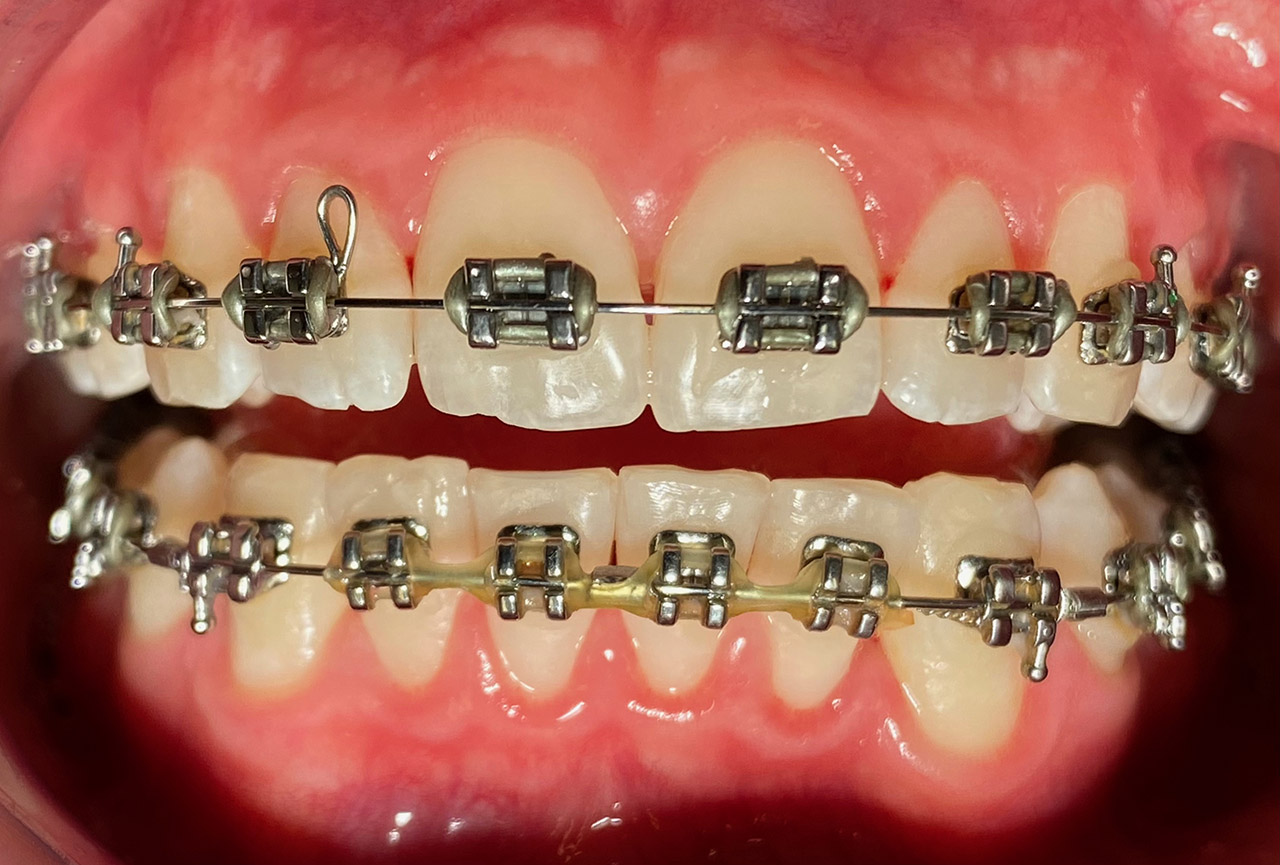

Prophylaxe/professionelle Zahnreinigung:

Zur Motivation, Information und Instruktion einfärben der Beläge (bakterieller Biofilm) bei jungem Patienten in kieferorthopädischer Behandlung.

Reinigung der Zähne mit Pulverstrahltechnik minimalinvasiv und zahnschonend und wo noch nötig gezielt mit Ultraschall.

Das Resultat 45 Minuten später.